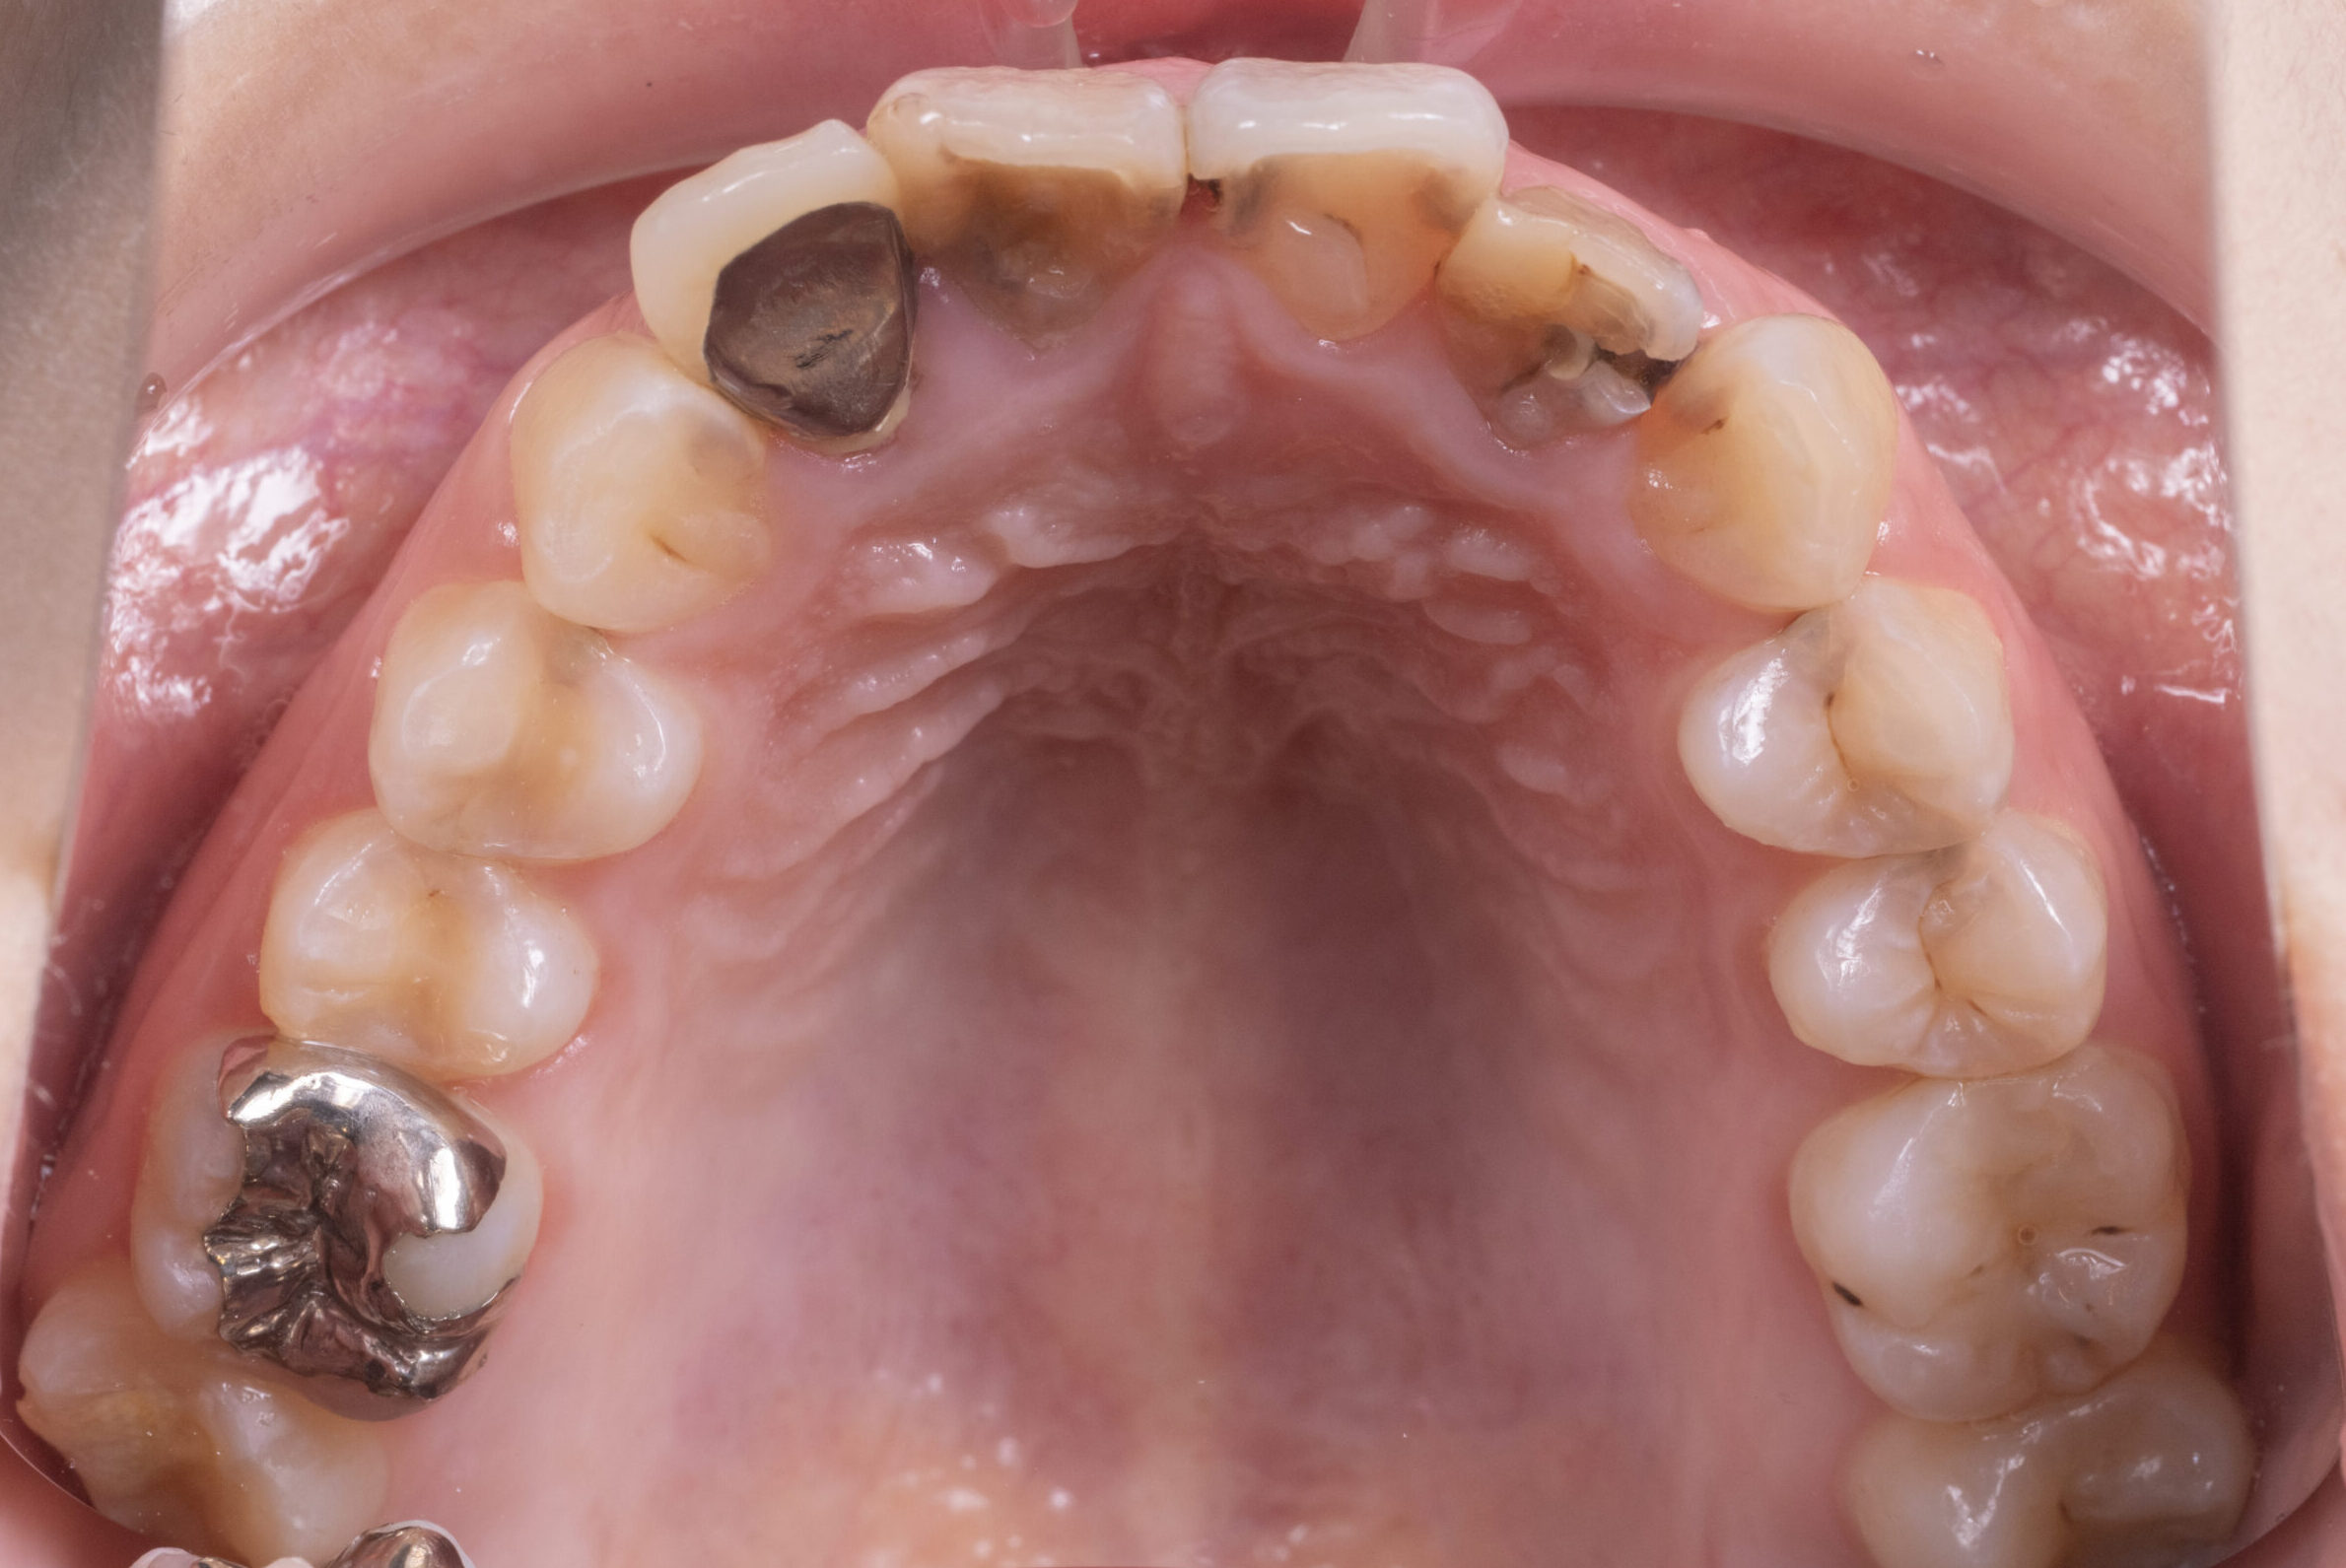

《初診時》

患者様の主訴は虫歯治療・詰め物が取れてしまった為ご来院されました。

虫歯治療と必要な箇所に根管治療を行いました。

【初診時】